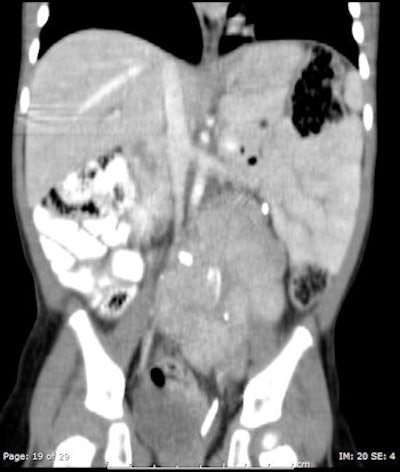

![Chest CT of 8-day-old girl with respiratory distress (80 kV, 51 average effective mAs, CTDIvol = 2.3 mGy, DLP [dose length product] = 33 mGy cm, E[effective dose] = 1.1 mSv. CT was performed to exclude congenital lung abnormalities because of family history and small volume lungs. Image shows ground glass opacity and septal lines consistent with respiratory distress syndrome. In all four figures, CTDIvol and DLP are expressed in terms of the 16 cm CT dosimetry phantom; these should be divided by approximately two to be expressed in terms of the 32 cm CT dosimetry phantom. Effective dose was calculated from DLP using conversion coefficients specific to this scanner and using the International Commission on Radiological Protection Publication 103 definition of effective dose. All images courtesy of Zoe Brady, PhD.](https://img.auntminnieeurope.com/files/base/smg/all/image/2012/08/ame.2012_08_15_08_57_30_715_2012_08_15_pediatrict_CT_pic1.png?auto=format%2Ccompress&fit=max&q=70&w=400)

The researchers compared average dose values at the Royal Children's Hospital (RCH) in Melbourne with international DRLs for common pediatric CT examinations. They found the use of 80 kV for both chest and abdomen/pelvis imaging in children younger than 5 years old leads to a significant dose saving, but conceded there is potential for dose optimization by reducing scan lengths for body examinations for children older than 5 years old. The plan now is to review these protocols to determine whether there is appropriate justification for the extended scan lengths.

The authors carried out a retrospective audit of patient records for pediatric CT brain, chest, and abdomen/pelvis exams. Demographic information, exam parameters, and dose indicators (volumetric CT dose index [CTDIvol] and dose-length product [DLP]) were collected for 220 patients: 100 for CT brain exams and 60 for each of the CT chest and abdomen/pelvis exams. Local DRLs (LDRLs) were derived from mean survey values and the effective dose was estimated from DLP values. The normalized CTDIvol values, mAs values, and scan length were assessed to better identify parameters that could be optimized.

The LDRLs across all age categories were 18-45 mGy (CTDIvol) and 250-700 mGy cm (DLP) for brain examinations; 3-23 mGy (CTDIvol) and 100-800 mGy cm (DLP) for chest examinations; and 4-15 mGy (CTDIvol) and 150-750 mGy cm (DLP) for abdomen/pelvis examinations. Effective dose estimates were 1.0-1.6 mSv, 1.8-13.0 mSv and 2.5-10.0 mSv for brain, chest, and abdomen/pelvis examinations, respectively. The RCH mean CTDIvol and DLP values were similar to or lower than international DRLs.